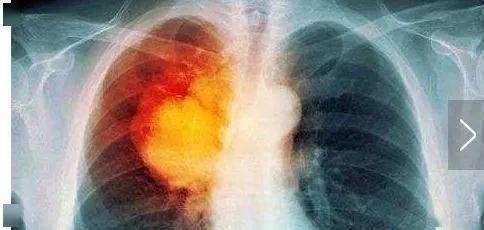

人体必需元素硒,能杀死癌细胞?适当吃6种食物,不怕身体少了它硒,一个听起来既陌生又神秘的元素,实则与我们每个人的健康息息相关。作为人体必需的15种微量元素之一,硒在抗氧化、增强免疫力、预防心血管疾病及某些癌症方面发挥着不可替代的作用。近年来,关于硒能“杀死癌细胞”的说法更是引起了广泛讨论。那么,硒究竟是如何影响我们的...

˙▽˙ 人体必需元素硒,可杀死癌细胞?医生:适当吃4种食物,不怕缺硒在日常生活中,我们常常会听到各种关于营养素的传言和说法,其中不少涉及人体微量元素的摄入。作为人体必需微量元素之一的硒(Se),常被赋予抗氧化、增强免疫力甚至“杀死癌细胞”的能力。然而,这些说法究竟有何科学依据?硒与人体健康之间存在怎样的联系?又有哪些食物可以帮...

人体必需元素硒,可以杀死癌细胞?适当多吃4种食物,不怕缺硒它真的能够杀死癌细胞吗?如何保证自己不缺硒?硒与健康的关系:杀死癌细胞?硒在体内的作用极其广泛。它是重要的抗氧化酶—谷胱甘肽过氧化物酶的组成部分,能够帮助清除体内的自由基,减缓细胞衰老,减少慢性病的发生。更为重要的是,硒在癌症的预防和治疗中展现出了令人惊讶的潜...

人体必需元素硒,能“杀死”癌细胞?日常该如何补充?听医生说硒并不能直接“杀死”癌细胞,而是通过多种机制抑制肿瘤的生长和发展。因此,硒的补充不能代替放化疗以及手术治疗。如果发现患有恶性肿瘤,还是需要到医院积极配合治疗,延缓肿瘤生长,提高生存期。那么,在日常生活中,我们该如何科学补充硒元素呢?根据世界卫生组织的建议,成人每...